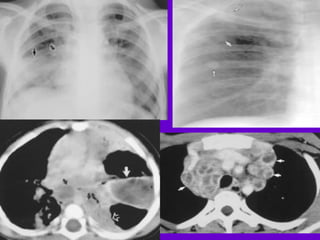

Pulmonary TB :

􀂄Lobar Pneumonia

􀂄 CT is superior than plain CXR in picking

up the

consolidation, atelectasis and the hilar LN

thereby

making the diagnosis easy.

􀂄 MRI reveals some of these changes,

however, CT is

the diagnostic modality of choice in such

cases.

􀂄Bronchopneumonia

Hilar and Mediastinal

Lymphadenopathy

􀂄 CT and MRI depict the hilar and

mediastinal LN

equally well.

􀂄 Calcification in the nodes is however

better seen on

CT.

􀂄 Necrosis is seen as focal areas of low

attenuation on

a CECT.

􀂄 On MRI focal necrosis is seen as areas

of increased

signal intensity on T2W images.

􀂄EBTB

􀂄 HRCT is sensitive in the detection of

early

endobronchial spread of disease.

CXR Findings

 Primary TB:

 Lower or middle lobe infiltrates

 Reactivated TB:

 Apical infiltrates/cavitation

 Latent TB:

 Usually normal

 Nodules in hilar area or upper lobes

 Pleural scarring/thickening